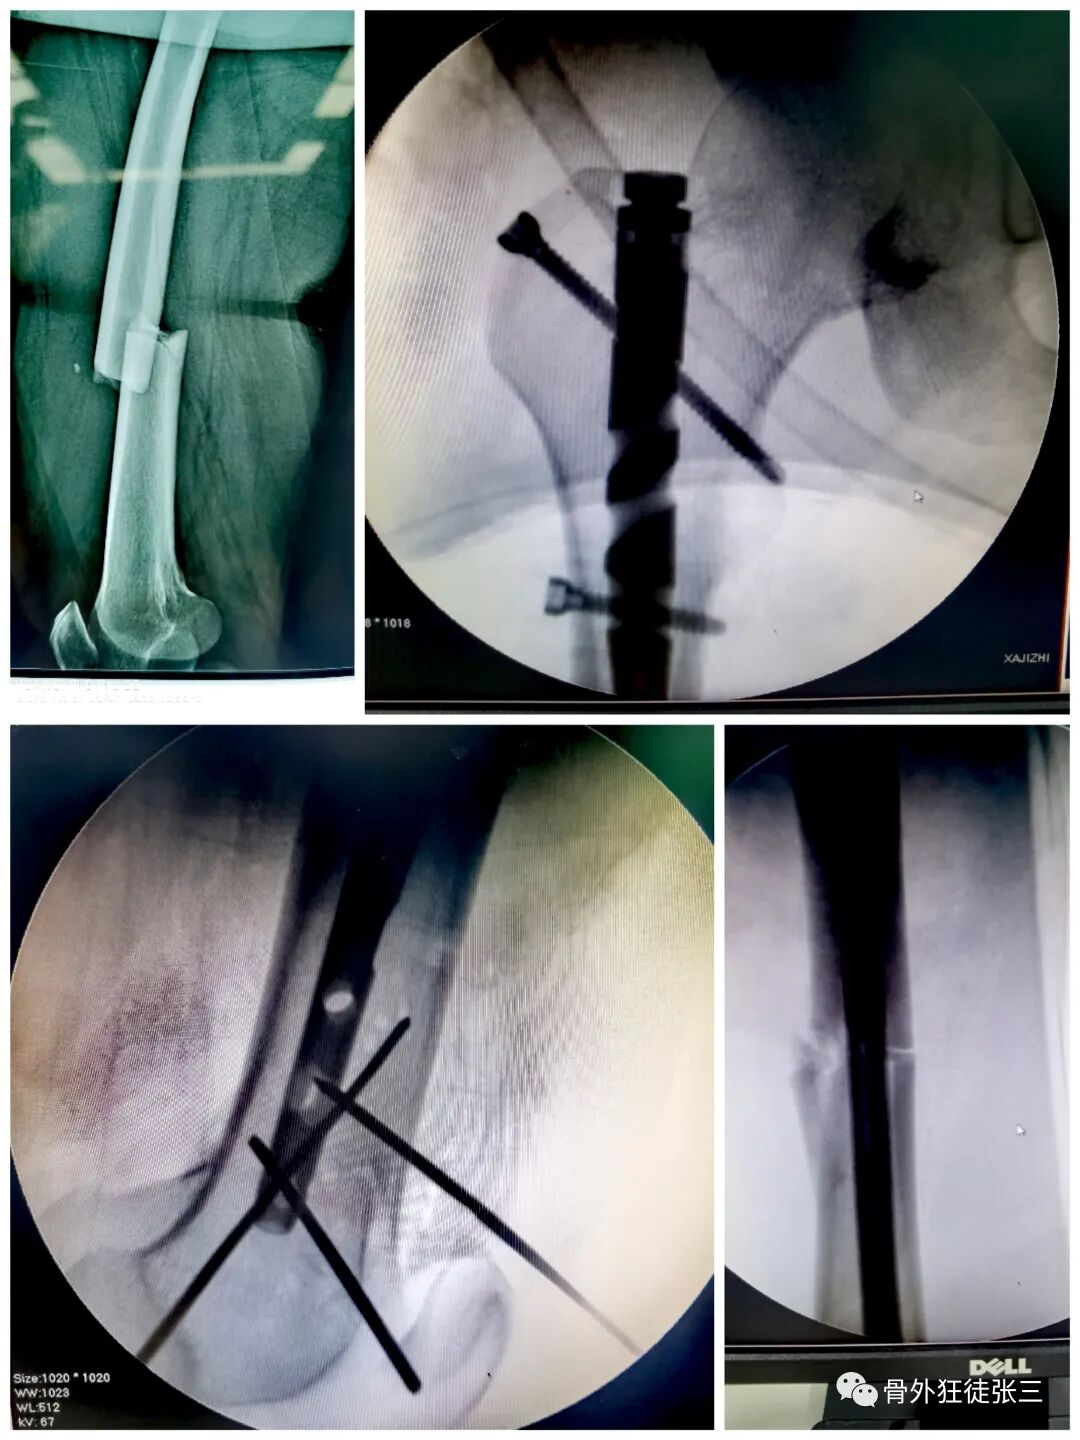

病例30,股骨干骨折,重建髓内钉,克氏针阻挡针,